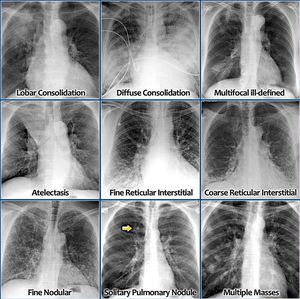

Different lung stage in various ways